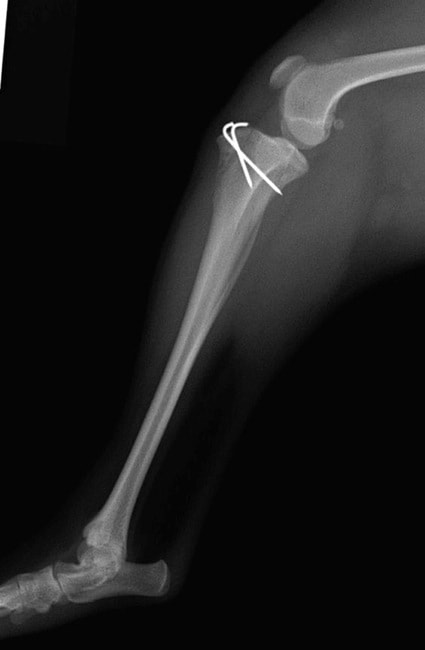

■ 症例24 キャバリア 7か月

左右膝蓋骨内方脱臼(左:グレードⅣ 右:グレードⅢ)

以前から左右後肢の跛行が認められ、整形外科学的検査・レントゲン検査により左右の膝蓋骨脱臼が認められた。症状が重度である左膝の膝蓋骨脱臼整復術を行った。外科手技は縫工筋及び内側広筋の解放、脛骨粗面の外側転位、滑車ブロック形造溝術、内外側関節方の縫縮を実施した。術後一か月時点で、左の膝蓋骨は安定しており経過は良好である。

本症例は成長期における重度の膝蓋骨脱臼であり、術後の再発の可能性もあるため、経過をしっかりと観察していく必要がある。また、今回手術を実施していない右膝に関しても経過を観察し、手術を検討していくこととする。